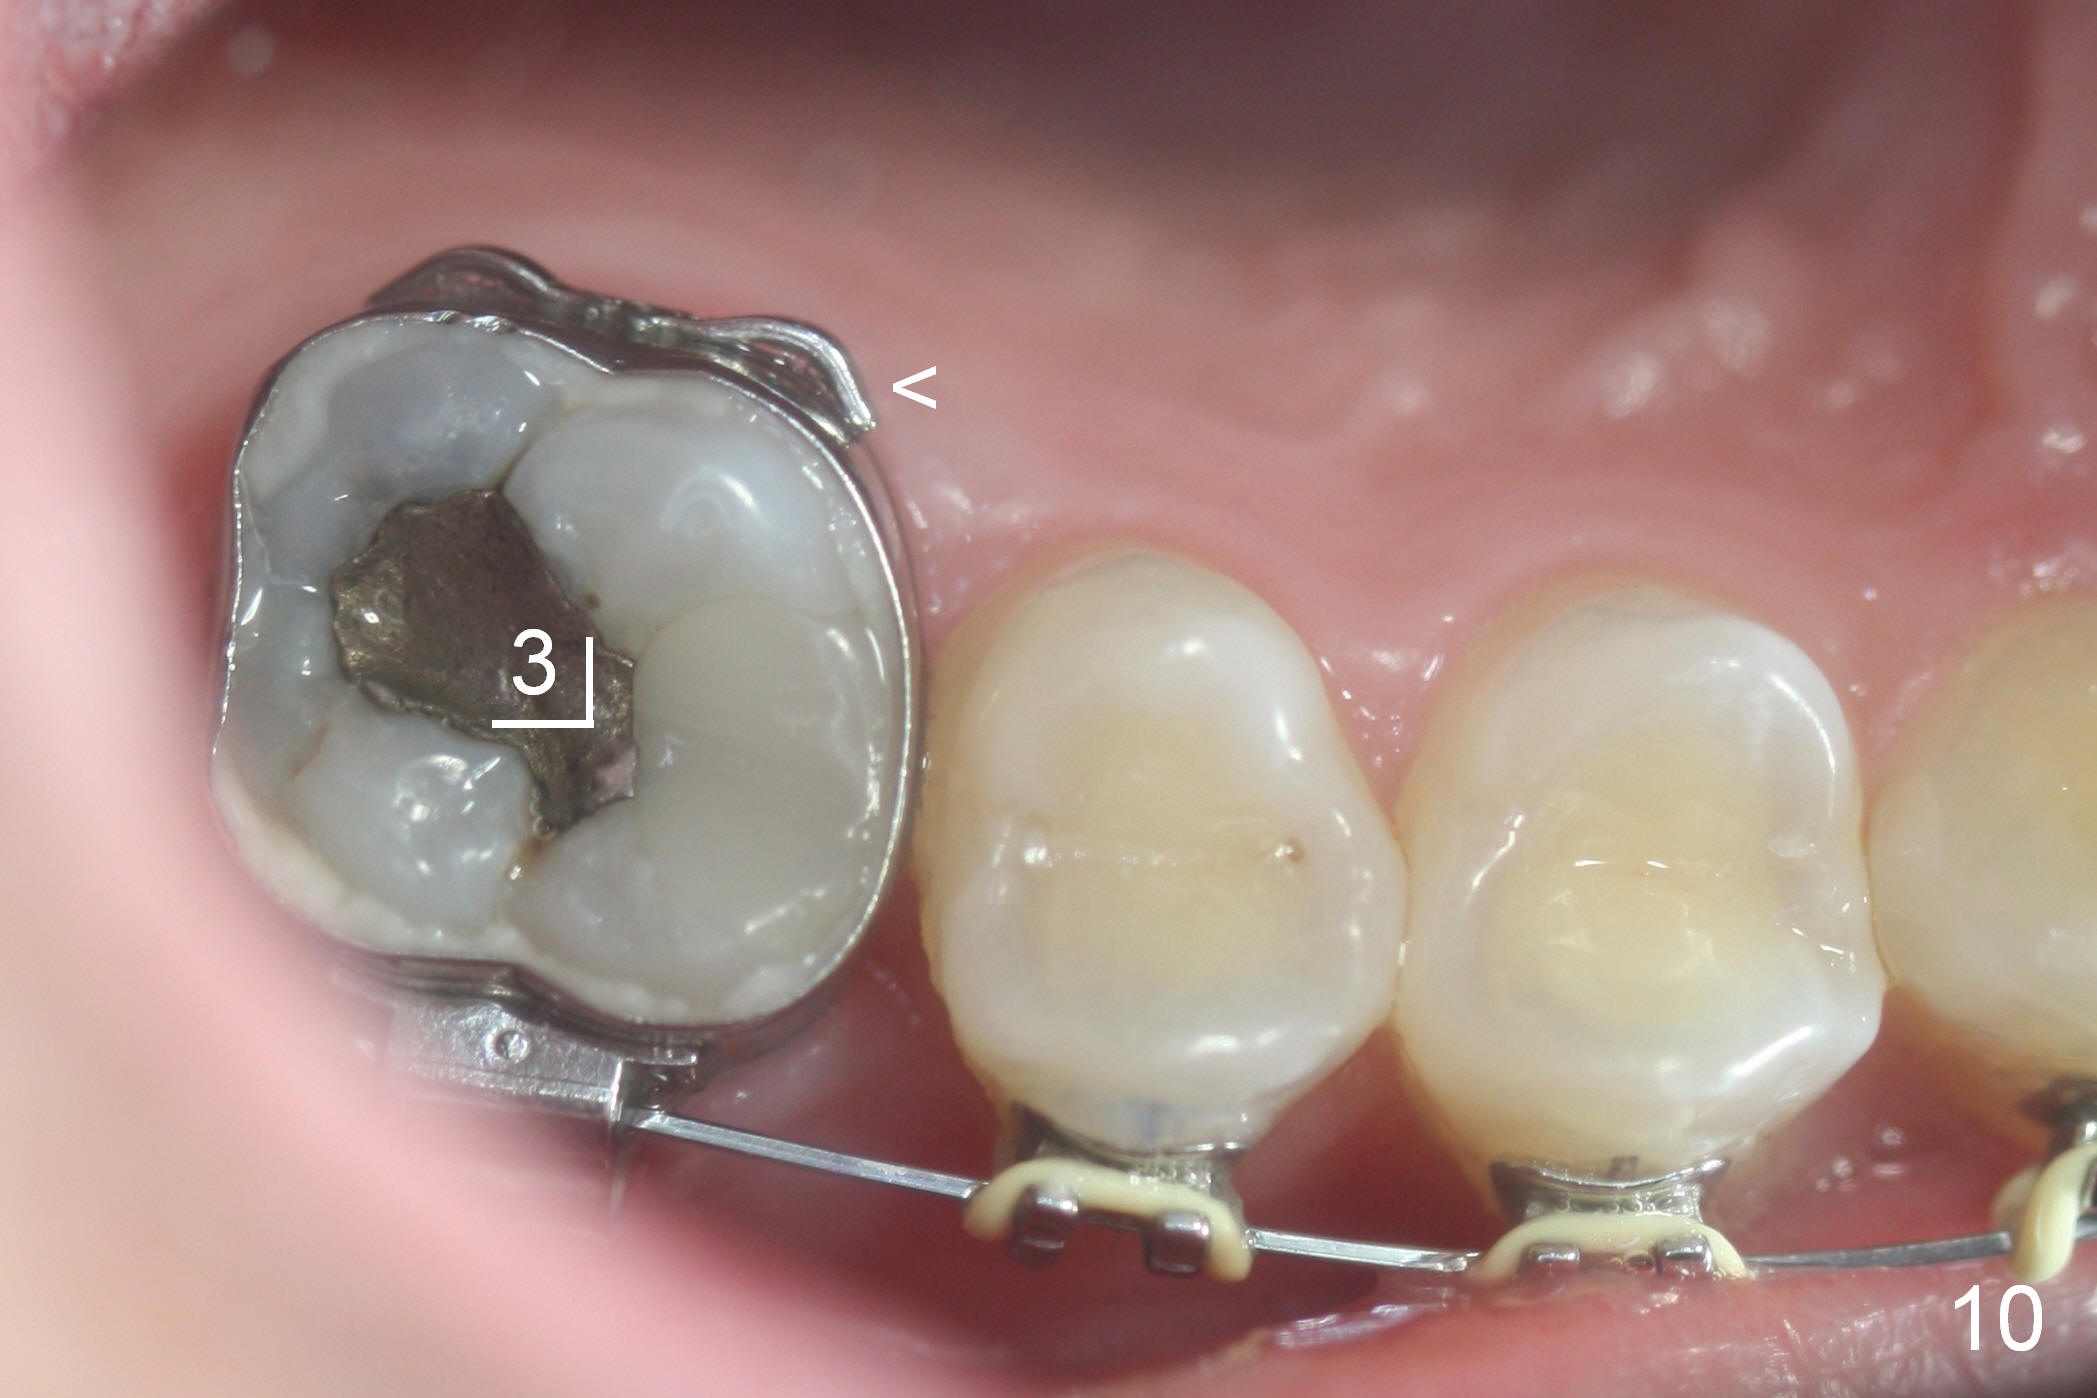

Two weeks later, it appears that U3s do not move distal (Fig.10,12), whereas the lower teeth do (Fig.11,13). Power chains change to 2 with grey ones. If no more change occurs in 1 week, change to next wires with power chains x 4 with one end attached to the lingual cleat (Fig.10,12 arrowheads) so that U3s may evenly (buccal and palatal) move distal. If LL3 keeps moving much faster than LR4, switch the closed coil springs.